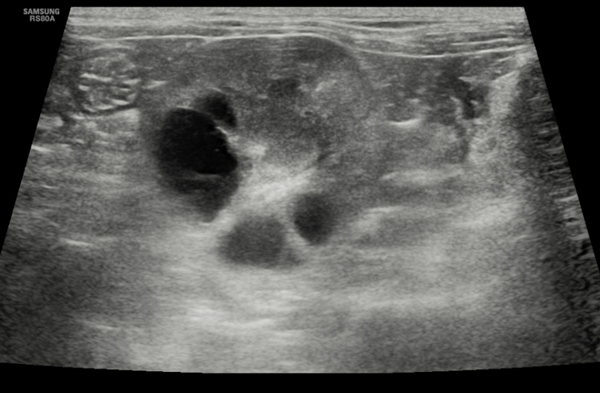

Figure 1. Transverse section of the left kidney of a five-year-old MN British short-haired cat showing multiple cysts in the cortex and medulla, consistent with a diagnosis of polycystic kidney disease.